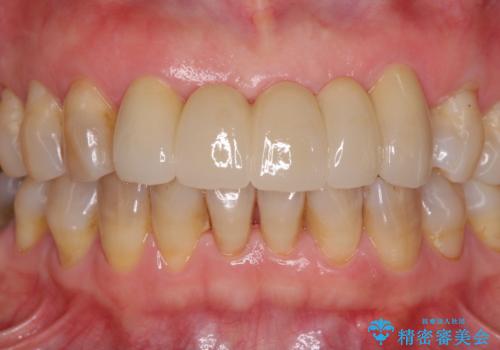

自然な仕上がりとするため、金属を使用しないオールセラミックブリッジにより補綴治療を行うこととしました。

装着されていたブリッジは、支台となっている歯と欠損している歯で色が大きく異なっていましたが、オールセラミックとしたことで、全体的に色調の整った仕上がりとなりました。

歯肉ラインがきれいに整い、患者様には大変満足していただきました。